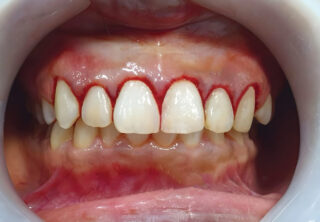

Gum disease, also known as periodontal disease, is a chronic inflammatory condition caused by bacterial plaque buildup along and below the gumline. In its early stage (gingivitis), gums may appear red, swollen, and bleed easily. If left untreated, it can progress to periodontitis, where inflammation damages the tissues and bone supporting the teeth, potentially leading to tooth loss.

Warning signs of gum disease include bleeding gums, persistent bad breath, gum recession, loose teeth, or changes in how teeth fit together. However, gum disease can progress with minimal discomfort, making regular dental exams especially important for individuals with diabetes.